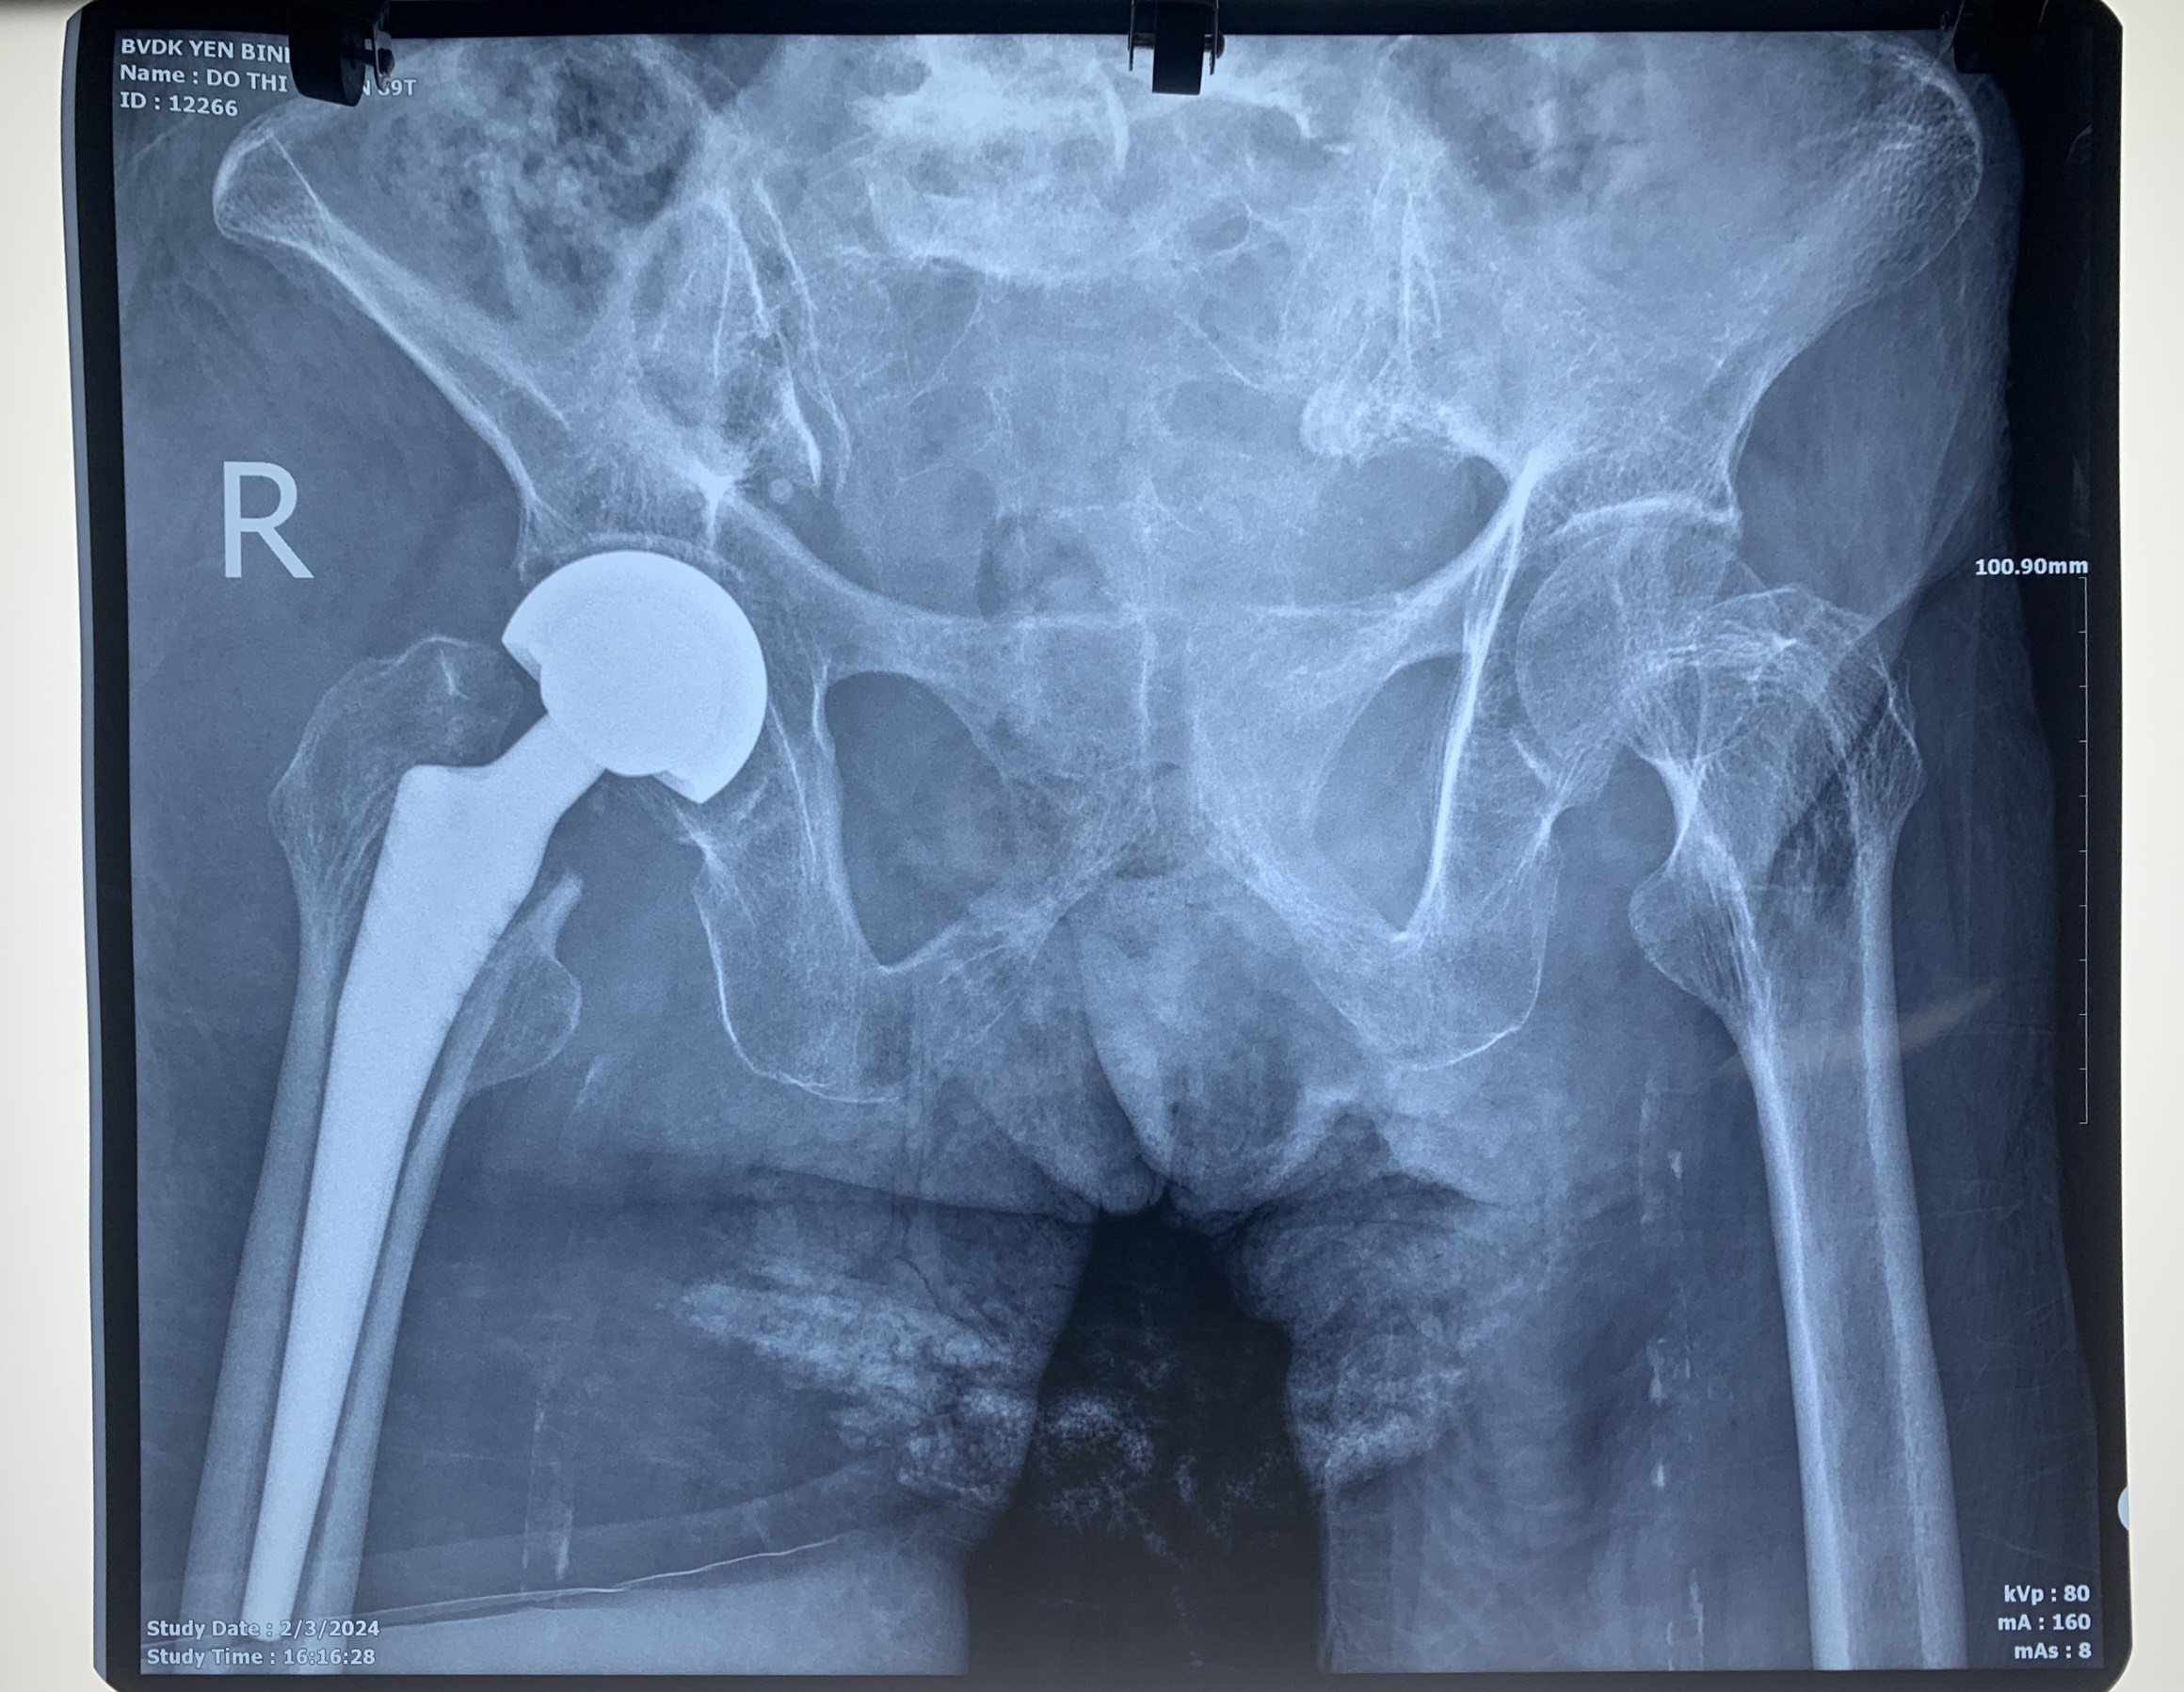

Patient D.T.T, 89 years old, located in Hong Tien ward, Pho Yen city. The patient fell and had a lot of pelvic pain so he went to Yen Binh Thai Nguyen General Hospital.

Doctors conducted examinations, ultrasounds, and X-rays and concluded: The patient had a broken right femoral neck. Doctors conducted a consultation and decided to perform right hip replacement surgery for the patient. The surgery was performed by the team of MSc. Specialist level 2 Nguyen Chi Duc, Deputy Director of Yen Binh Thai Nguyen General Hospital. After surgical treatment, the patient’s health is currently stable.

X-ray image of patient D.T.T after surgery